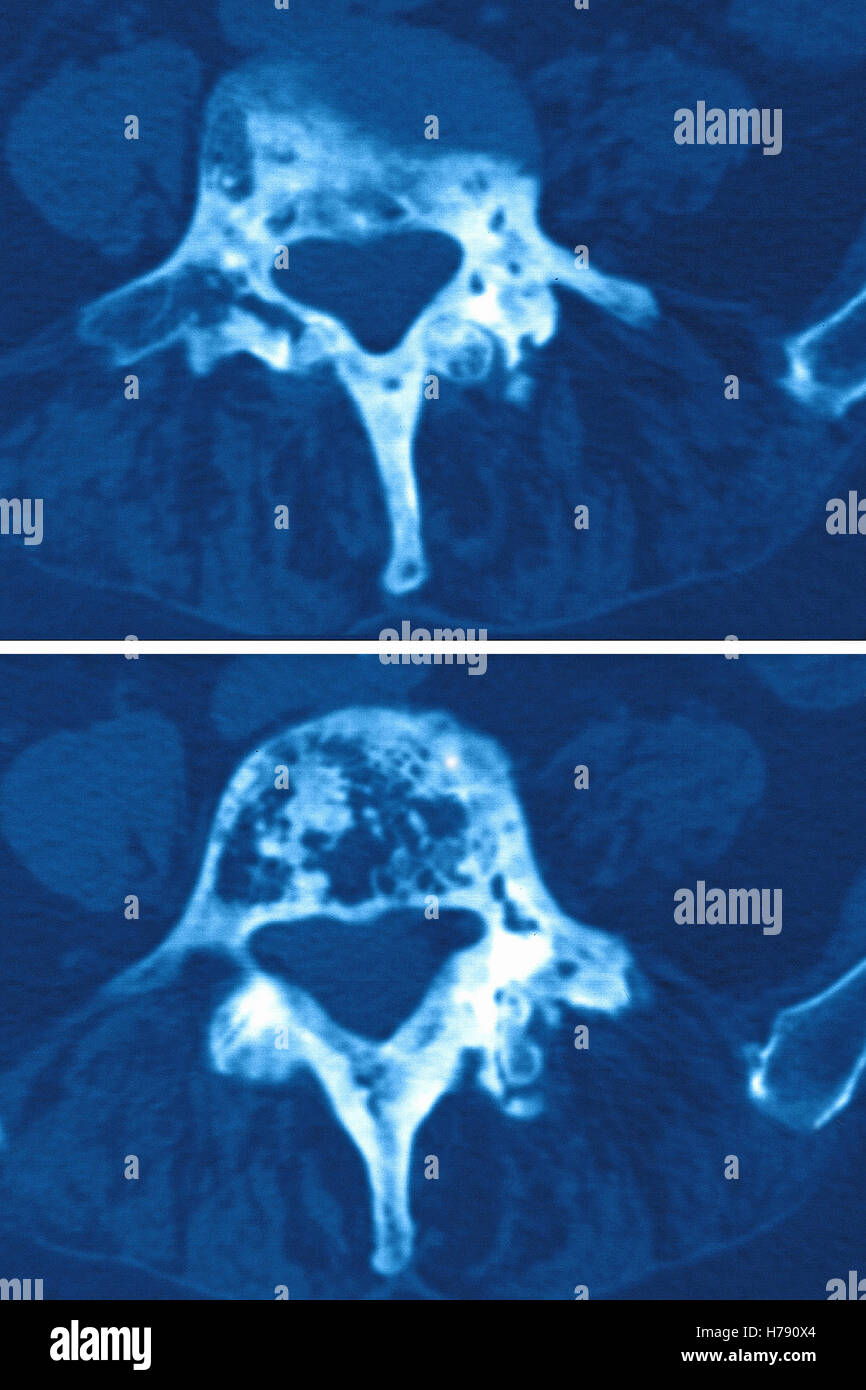

Morbo di Paget

maladie de paget radio Ericvisser